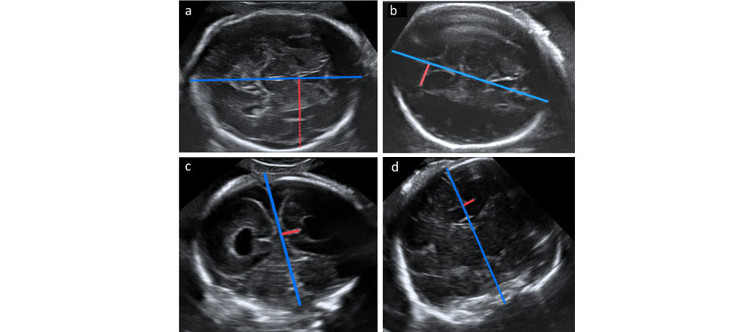

La dilatación ventricular puede estar relacionada con cambios en el desarrollo cortical en los fetos con ventriculomegalia aislada